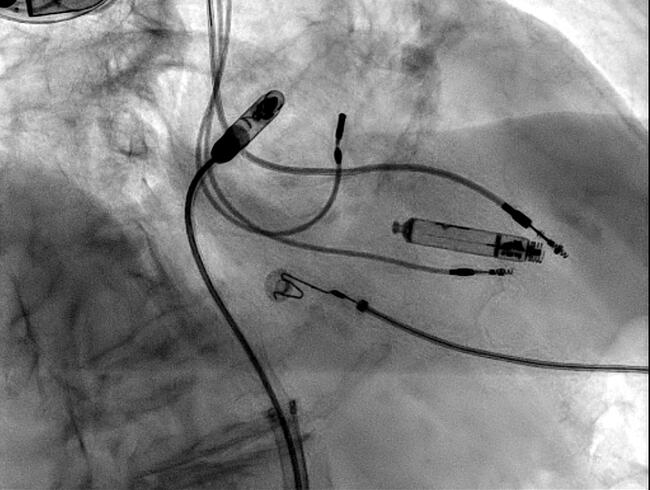

The AVEIR catheter was advanced through the 25 French introducer sheath to the right atrium, and gently navigated through the tricuspid valve

and into the RV (Figure 2). Contrast-enhanced cine images in left and right anterior oblique projections confirmed appropriate low septal positioning (Figure 3). Passive mapping demonstrated excellent injury current.